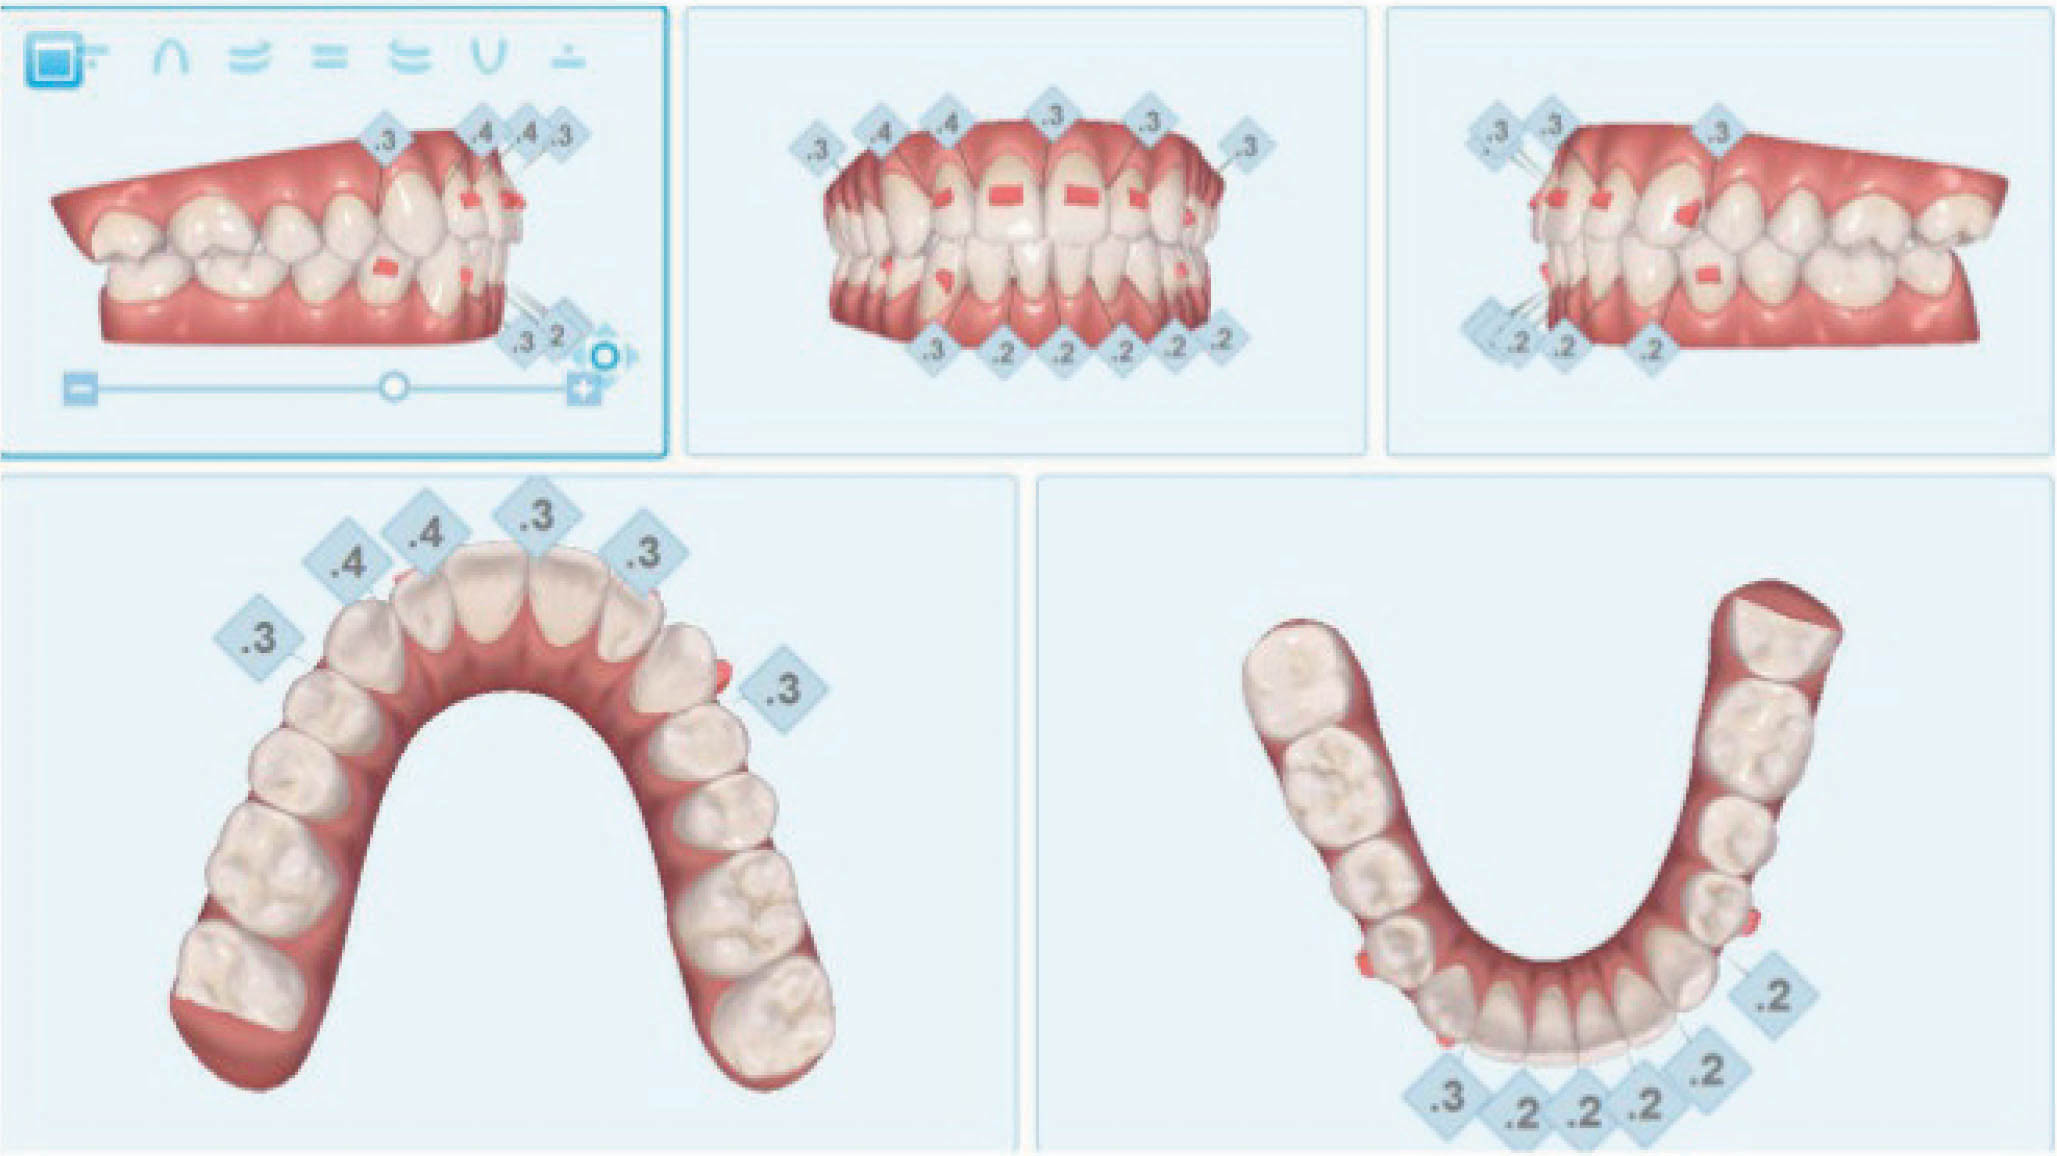

بیمار بعدی یک بیمارکلاسI با میزان متوسطی از کرادینگ در هر دو فک است. به کانینهایی که شدیداً چرخیدهاند دقت کنید (شکل 15-6 تا 17-6). این بیماران به ارتودنسی شفاف عالی جواب میدهند. یک دختر دبیرستانی که نمیخواهد در جشن فارغ التحصیلی خود و عکسهایی که در کلاس میگیرد براکت داشته باشد، خیلی خوب از الاینرهای شفاف استفاده میکند.

I. مشخص کردیم که بیمار غیرکشیدنی درمان بشود.

II. درمان کرادینگ با ترکیبی از روشهای زیر انجام بشود:

A. اکسپنشن خلفی

B. پروترود نمودن انسیزورها

C. استریپ بین دندانی

یکی از خوبیهای طراحی کامپیوتری این است که دکتر میتواند میزانهای متفاوتی از اکسپنشن، پروترود نمودن انسیزورها یا استریپ را قبل از شروع کار مشاهده نماید. با این نوآوری میتوانید نتیجه کار و مسیر حرکت دندانها از ابتدا تا انتهای درمان را کنترل نمایید. عرض بین کانینی در مندیبل را هم ثابت نگه داشتیم تا حداکثر ثبات درمان را داشته باشیم. به همین دلیل از ترکیبی از اکسپنشن، پروتروژن انسیزورها و استریپ استفاده نمودیم. اگر به شکل 18-6 که قبل از درمان قوس پایین است نگاه نمایید، سانترال پایین که خیلی لبیالیتر از جایگاه اصلی خود میباشد را میبینید. بنابراین این دندان باید حرکت لینگوالی کند.

• حداکثر 3mm اکسپنشن خلفی در دیستال کانین بدهید (هر سمت1.5mm).

• هر کانتکت در قدام پایین تا 0.3mm حداکثر میتواند استریپ بشود.

• لترالهای چپ و راست پایین میتوانند پروترود بشوند، ولی سانترال راست پایین باید 1mm لینگوالیتر از موقعیت فعلی خود قرار بگیرد.

به کانین بالا که شدیداً چرخش دارد توجه کنید (شکل 19-6). علیرغم چرخش شدید، این دندانها به راحتی به چهار دلیل زیر خواهند چرخید و عالی میشوند.

• اتچمنتهایی برای اصلاح چرخش روی این دندانها قرار گرفته تا اعمال نیرو مناسبی برای حرکات مطلوب دندانی داشته باشیم.